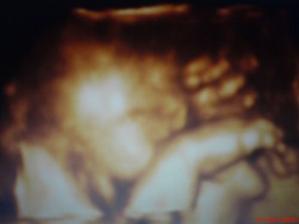

Karolínka :o)

naše neplánované mimíško,tuším holčičku a tu mi Dr.20 tt potvrdil :o)...termín porodu 19.12.2007